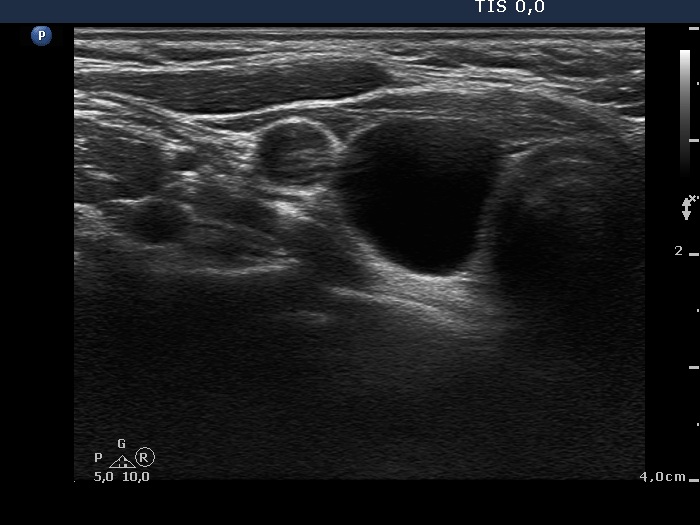

Ultrasonography: the thyroids were echonormal. There was a cystic lesion in the lower-dorsal part of the right lobe.

Ultrasonography: the thyroids were echonormal. The cyst has recurred.